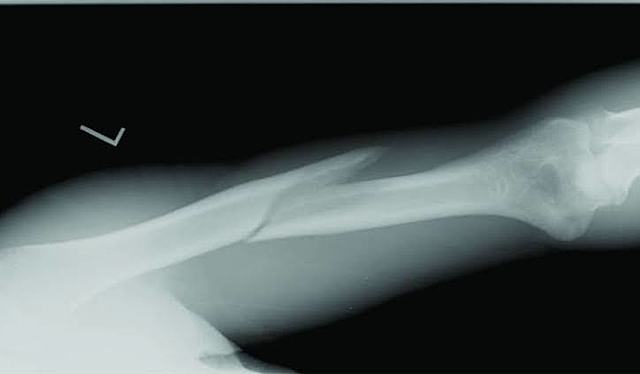

• Tomografía de brazo fracturado

Tomografía de brazo fracturado

En febrero de 1896 tomo una radiografía de un brazo fracturado y la mando al British Medical Journal extraordinario poder diagnostico